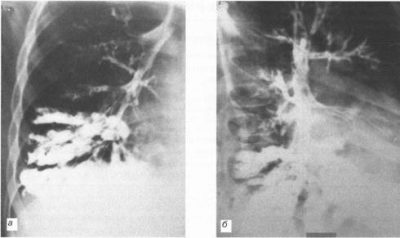

- Бронхоэктазы представляют собой мешотчатые стойкие расширения мелких дистальных бронхов и бронхиол. Приобретенные бронхоэктазы значительно ухудшают течение ХОБЛ. В бронхиальных расширениях постоянно присутствует инфекция, отхождение мокроты из них крайне затруднено. В результате обострения наступают все чаще. Клинически бронхоэктазы ничем не отличаются от признаков обструктивного бронхита.

-

Пневмофиброз и пневмосклероз, как исход пневмонии, приводят к значительной потере паренхимы легкого и выключению части органа из процесса дыхания. Фиброзный тяж представляет собой участок разрастания соединительной ткани на месте хронического гнойного процесса.

Результатом пневмосклероза является нарастающая одышка, прогрессирование возрастания давления в легочных сосудах и застойных явлений в большом круге кровообращения. Усиливается цианоз, нарастает слабость, появляются отеки. Бронхоэктазы характерны для бронхитического типа ХОБЛ, а склерозирование легких – для эмфизематозного.